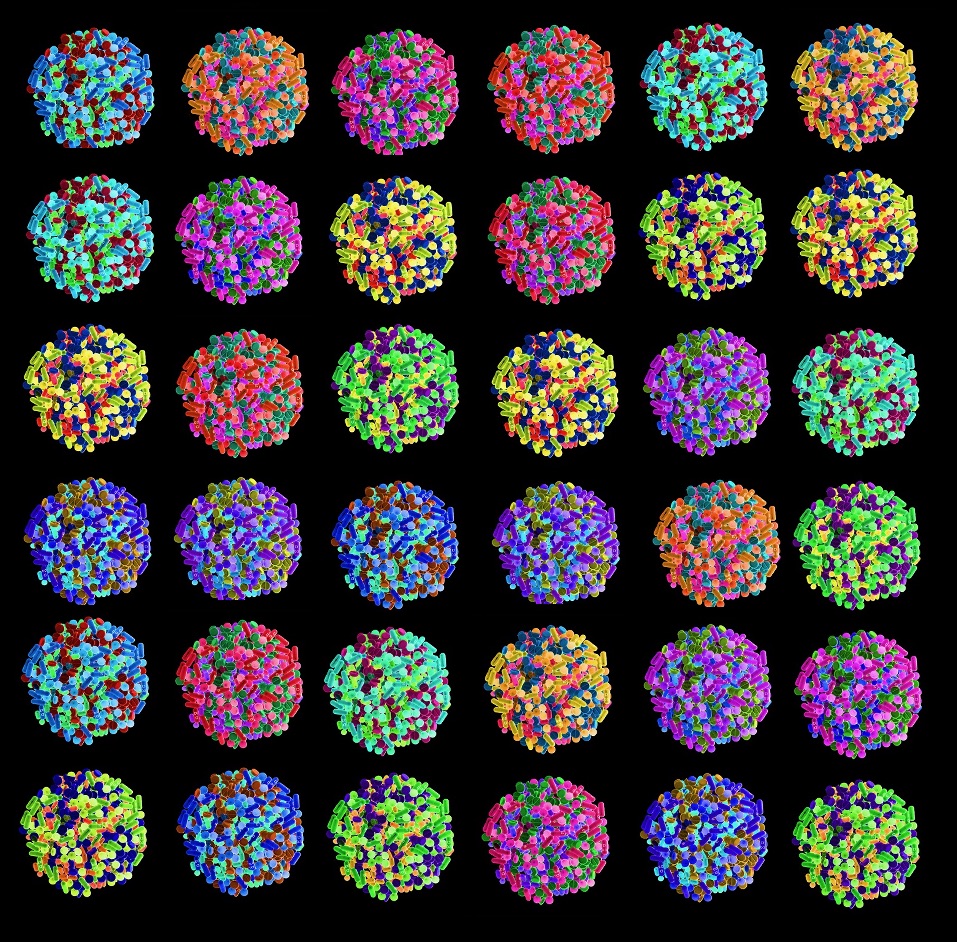

In my frustration I dumped a bunch of those pills out they were pretty, I snapped a pic. The meds I was to discontinue got their farewell by being crushed, I took a pic. I liked it, it made me feel like something other than a patient. I spelled out symptoms with their corresponding pills, sometimes taking hours more pictures.

I had wanted to be one of those cool artists that did photo diaries or Vlogs of the whole illness. I was far too out of it, between the pain and the meds, to even think about doing something like that. With help, I began digitally manipulating them to make them more colorful and textural, it gave me hope amidst the mess.